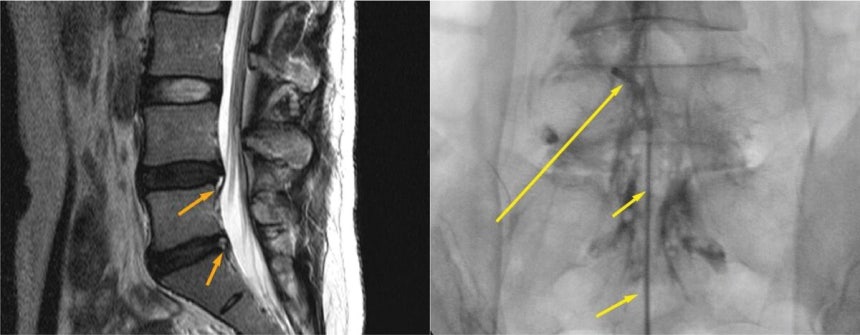

대표적인 방법이 신경차단술과 신경성형술이다. 신경차단술은 신경 주변에 약물을 주입해 염증과 부종을 가라앉히는 방식이고, 신경성형술은 특수 카테터를 삽입해 유착을 풀고 염증을 직접 제거한다.